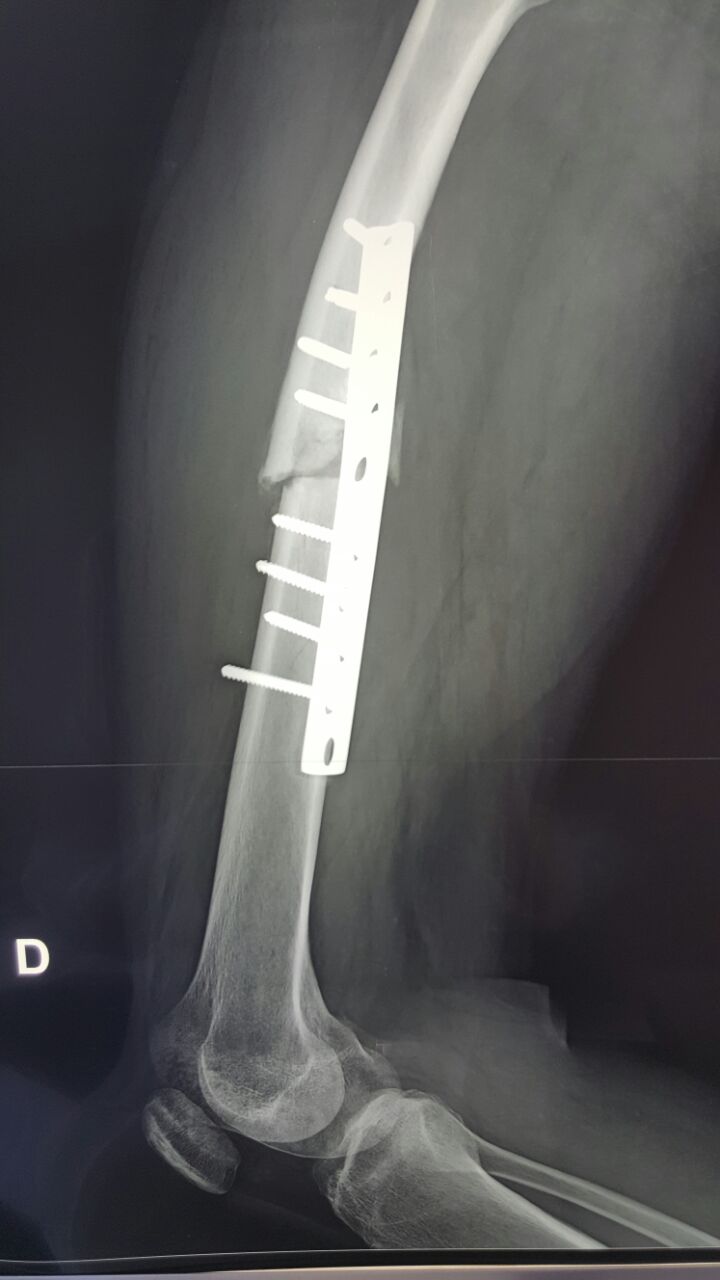

Снимки

А почему первично выбран не закрытый интрамедуллярный остеосинтез, а накостный?

Конечно, и сейчас оптимально убрать пластину минимально инвазивно, и закрыто синтезировать блокируемым гвоздем с минимальным рассверливанием.

Пластина обречена изначально, менять пластину на пластину неправильно, мининвазивное удаление, риммирование БИОС UFN

А почему Вы решили, что пластина обречена изначально? Сдесь просто была слишком короткая пластина и Недопустимая раняя нагрузка для данного случая. гвоздь, конечно, лучше. Но и пластинку можно. Если все по правилам. А гвозди то же иногда " обрекаются"

потому и обречена, что короткая, недостаточная рабочая длина,в представленном вами случае неадекватный диаметр импланта и , возможно, непроведенная вовремя динамизация(хотя, судя по блокировке овального отверстия в статике, возможности динамизации и не предполагалось). А чтобы синтезировать LC-DCP такие диафизарные переломы, надо ОЧЕНЬ сильно их(пластны) любить, а больных наооборот - не очень

Просто интересно, зачем вы предплагаете пластику губчатой костью? Это еще и не ложняк, а несостоятельный синтез.

всем доброго времени суток! по-моему изначально не правильно были введены винты: пластина не работала на компрессию, а наоборот на диастаз. от туда и потеря стабильности.(интересно посмотреть более ранние снимки). я за гвоздь!

Есть, конечно, показания и для остеосинтеза пластиной переломов бедра, однако, данный случай, похоже, не из этой категории.

Правильно и то, что на настоящий момент мы имеем дело с несросшимся переломом бедренной кости и несостоятельным остеосинтезом.

Мне бы казалось правильным в данном конкретном случае удалить металл (уж не знаю, насколько малоинвазивно, учитывая перелом винтов) и выполнить остеосинтез толстым стержнем с рассверливанием канала.